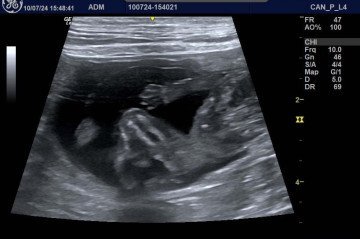

Mas para confirmar a gravidez e monitorar a saúde dos filhotes, é preciso consultar um profissional, que irá direcionar exames e a melhor forma para prosseguir. O ultrassom, por exemplo, é o método mais precoce para confirmar a gestação, podendo ser realizado a partir de 15 a 20 dias em cadelas e gatas. "A ultrassonografia é um excelente método para acompanhar a viabilidade dos filhotes. Ele permite visualizar os batimentos cardíacos, avaliar o desenvolvimento dos órgãos e identificar possíveis malformações", explica a ultrassonografista veterinária Marcela Marques. Além disso, a possibilidade de visualizar os filhotes encanta a maior parte dos tutores.

O ambiente deve permanecer calmo e seguro, com acompanhamento discreto. Se as contrações persistirem sem a expulsão de filhotes ou houver qualquer sinal de dificuldade, é fundamental procurar atendimento veterinário. "Por isso, é muito importante avaliar previamente a quantidade e a viabilidade dos fetos, por meio de ultrassom ou raio-X, nos dias que antecedem o parto. Assim, o tutor pode acompanhar o nascimento em casa com mais tranquilidade, sabendo que todos os filhotes esperados foram expelidos e que a fêmea está bem", explica Rafael.